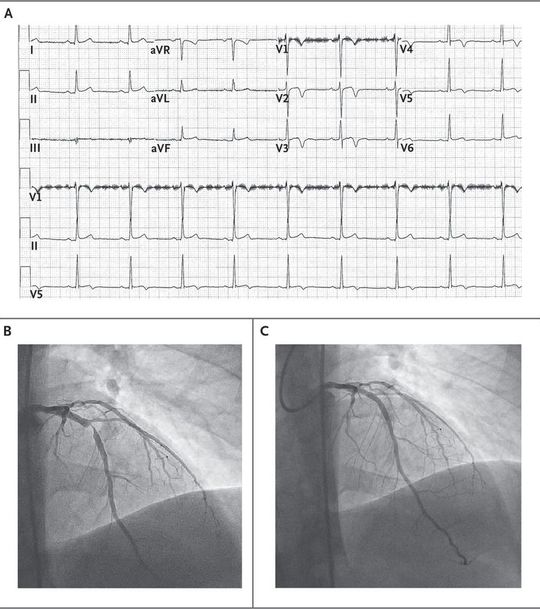

A 31-year-old male smoker with diabetes mellitus presented to the emergency department with intermittent, exertional chest pain of 4 days' duration. Electrocardiography performed on arrival (Panel A) revealed anterior T-wave inversions with biphasic lateral T waves, which raised concern about Wellens' syndrome, a syndrome that is associated with severe stenosis of the left anterior descending artery. (The artifact in lead V1 is unrelated to Wellens' syndrome.) The initial troponin I concentration was 0.07 ng per milliliter (reference range, 0 to 0.03 ng per milliliter); it rose to 0.58 ng per milliliter at 6 hours and peaked at 0.79 ng per milliliter before intervention. Coronary angiography performed 12 hours after presentation showed stenosis of 95% of the mid–left anterior descending artery (Panel B), which was successfully treated with a drug-eluting stent (Panel C). The patient was found to have uncontrolled diabetes, with a glycated hemoglobin level of 11.9%. He had an unremarkable course after revascularization, with a preserved left ventricular ejection fraction, and was discharged after receiving smoking-cessation counseling, intensive diabetes education, and a cardiac rehabilitation referral.